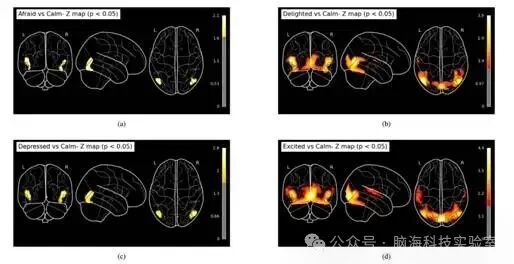

各对比条件的统计图均使用 SPM 进行计算,并借助 Python  Nilearn 进行可视化。

在一级分析基础上,采用单样本 t 检验进行二级分析,分别以“平静”作为基线,对“恐惧、欣喜、抑郁、兴奋”四种情绪进行对比。

10 不同对比条件的 z 值图(阈值 p < 0.05

(a) 恐惧 vs. 平静 (b) 欣喜 vs. 平静  (c) 抑郁 vs. 平静  (d) 兴奋 vs. 平静

根据 fMRI 分析结果,研究人员分别计算了以下四种情绪对比在大脑双侧(左、右半球)的激活图:恐惧 vs. 平静、欣喜 vs. 平静、抑郁vs. 平静、兴奋 vs. 平静

9 展示了这些对比的正、负激活图,色标对应 z 值,阈值设为 p < 0.05;图 10 则给出了仅显示正激活的 z-map。表 7 汇总了每个对比中前四个最大团簇的统计信息,包括峰值 MNI 坐标、峰值 z 值及对应的 AAL [39] 脑区标签。

从表 7 可见:恐惧 vs. 平静:中颞叶(Temporal_Mid)与枕下回(Occipital_Inf)显著激活,提示这些区域在恐惧加工中活动增强。欣喜 vs. 平静:激活集中在顶下小叶(Parietal_Inf)与中扣带回(Cingulate_Mid),表明感觉与情绪处理网络共同参与。抑郁 vs. 平静:顶上小叶(Parietal_Sup)与中扣带回(Cingulate_Mid)占主导,反映注意与情绪调节区域的活动改变。兴奋 vs. 平静:颞上回(Temporal_Sup)及颞叶区域显著激活,揭示听觉与情绪整合在兴奋状态下的增强,体现了各情绪状态独特的神经模式。